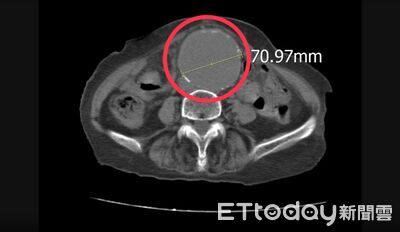

台中一名女性左腳痠痛不已,前往急診就醫,經超音波檢查,赫然發現腹主動脈有一顆超大腫瘤,已達7公分之大,經緊急手術治療後已康復出院。平等澄清醫院急診室主治醫師孫秀正表示,腹主動脈瘤被稱為「沉默的殺手」,有些人可能只出現腹痛、腰痛、背痛或下肢疼痛,很容易被誤認為肌肉痠痛或關節問題,一旦破裂,死亡率極高。 《詳全文...》